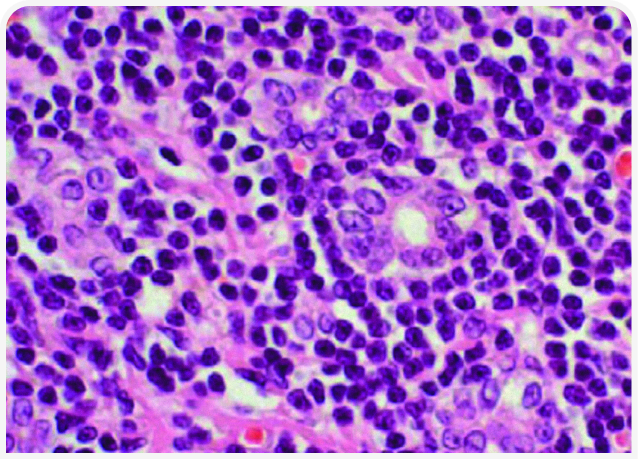

После постановки окончательного (см. гистопатологическую картину на Рисунке 3) или предположительного (как в клиническом случае) диагноза «лимфоцитарный холангит» лечение будет включать неспецифическую поддерживающую терапию и иммунную терапию. К неспецифической терапии относятся инъекции нескольких доз витамина K1 (5 мг на кошку подкожно каждые 24 часа) для нормализации показателей свертывания крови перед проведением тонкоигольной аспирационной биопсии или установкой эзофагального зонда и урсодезоксихолевая кислота (10-15 мг/кг внутрь каждые 24 часа в течение 2-3 месяцев). Этот препарат традиционно используют для стимуляции выведения желчи из билиарной системы; он обладает также рядом дополнительных положительных свойств для пораженной ткани печени (21).

При иммуноопосредованной инфильтрации лимфоцитами назначение антибиотиков не требуется. Даже если изначальной причиной заболевания была бактериальная инфекция, на момент обследования она уже разрешилась. Тем не менее некоторые врачи рекомендуют 2-4-недельный курс антибиотикотерапии в начале лечения для нейтрализации кишечных и/или анаэробных бактерий (см. Клинический случай 2), которые могут являться не причиной, а следствием иммуноопосредованного заболевания (19).

В качестве раннего и эффективного вмешательства у всех кошек, отказывающихся от корма, рекомендуется кормление через эзофагеальный зонд (Рисунок 4). Установка зонда также помогает владельцу ухаживать за кошкой на дому. В Университете Колорадо используют троакар и эзофагеальный зонд калибра 14Fr или производства MILA International, Inc.1

Специфическое лечение лимфоцитарного холангита заключается в назначении глюкокортикоидов, препаратом выбора считают преднизолон. Некоторые врачи начинают с дозы 4 мг/кг/день, большинство – с дозы ближе к 2 мг/кг/день, но во всех случаях дозу медленно снижают в течение 3 месяцев.